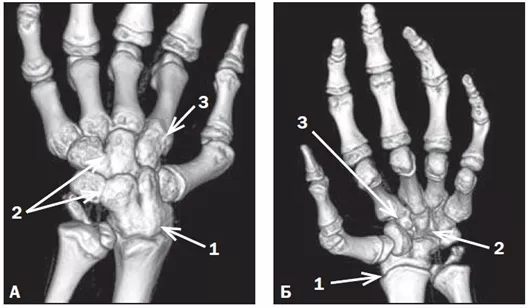

Рентгенография суставов: сужение суставных щелей и эрозии кости в лучезапястных суставах, мелких суставах кистей, стоп и плечевых суставах появляются в течение первых двух лет течения болезни. В костях запястья разрушение хряща происходит в проксимальном запястном суставе и интеркарпальных суставах, что приводит к карпальному анкилозу и укорочению конечности (фото 12). Также часто развивается атланто-аксиальное переразгибание.

Фото 12 (А, Б). Анкилозы в костях кисти при полиартикулярном ЮИА РФ-позитивном. КТ, 3D-реконструкция: А — тыльная сторона, Б — ладонная сторона. Деформация и нарушение положения костей кисти за счет анкилоза лучезапястного (1), межзапястных (2), II запястно-пястного (3) суставов [4].